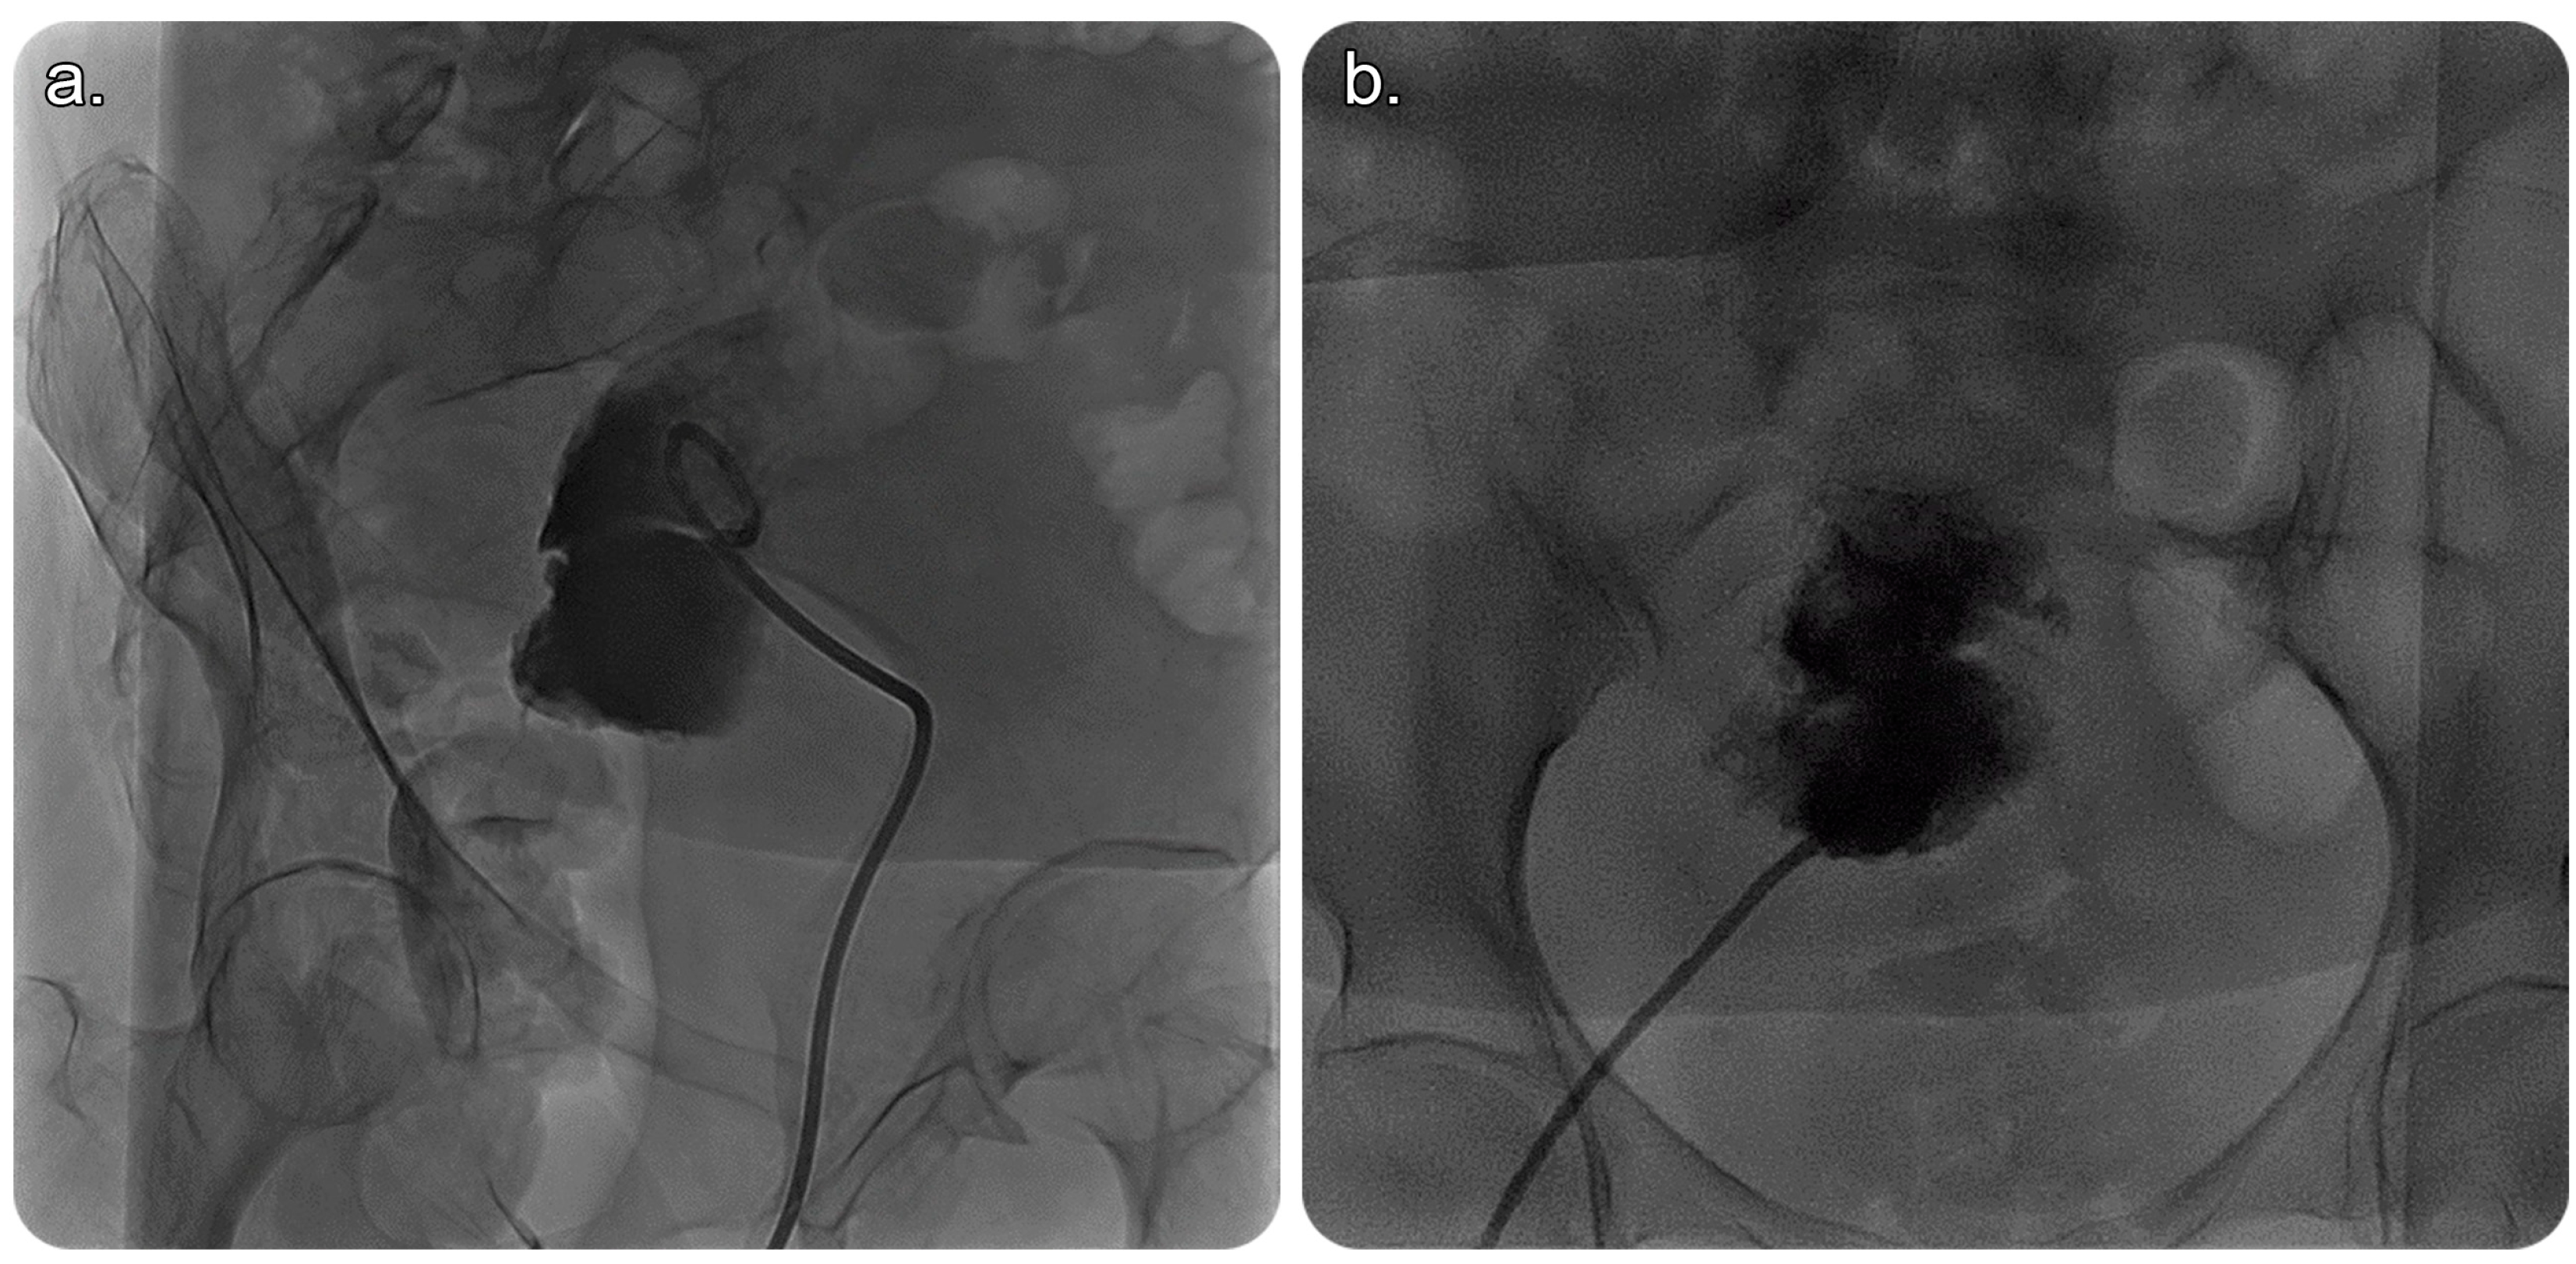

2. Case Presentation